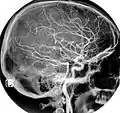

هر سرخرگ کاروتید مشترک به دو سرخرگ کاروتید داخلی و خارجی تقسیم می شود که سرخرگ کاروتید درونی باعث خونرسانی به نواحی پیشین مغز میگردد. نامهای دیگر سرخرگ کاروتید مشترک عبارتند از خوابرگ مشترک و شریان سُبات مشترک.

سرخرگهای کاروتید مشترک راست و چپ در ناحیه گردن به دو شاخه انتهایی تقسیم میشوند:

- سرخرگ کاروتید درونی که شاخهای در گردن ندارد

- سرخرگ کاروتید بیرونی